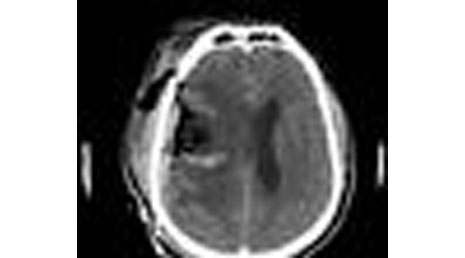

28. Extradural hematoma